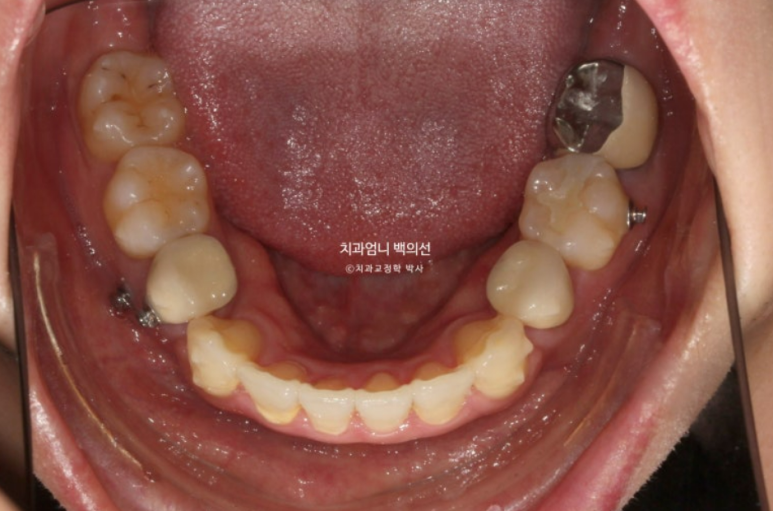

치료시작 9개월째 발치공간이 1/3가량 줄어든 모습입니다.

장치 협조도가 좋은 환자분이었습니다.

치료 도중 앞니 교합 깊어짐이 보여 앞니에 교정용 나사인 미니스크류를 심고 고무줄을 걸면서 앞니 수직적 컨트롤을 도모합니다.

이렇게 원래 치료계획에는 없던 부분이지만 치료 중간 모니터링 후 추가장치나 고무줄이 필요한 경우가 있습니다.